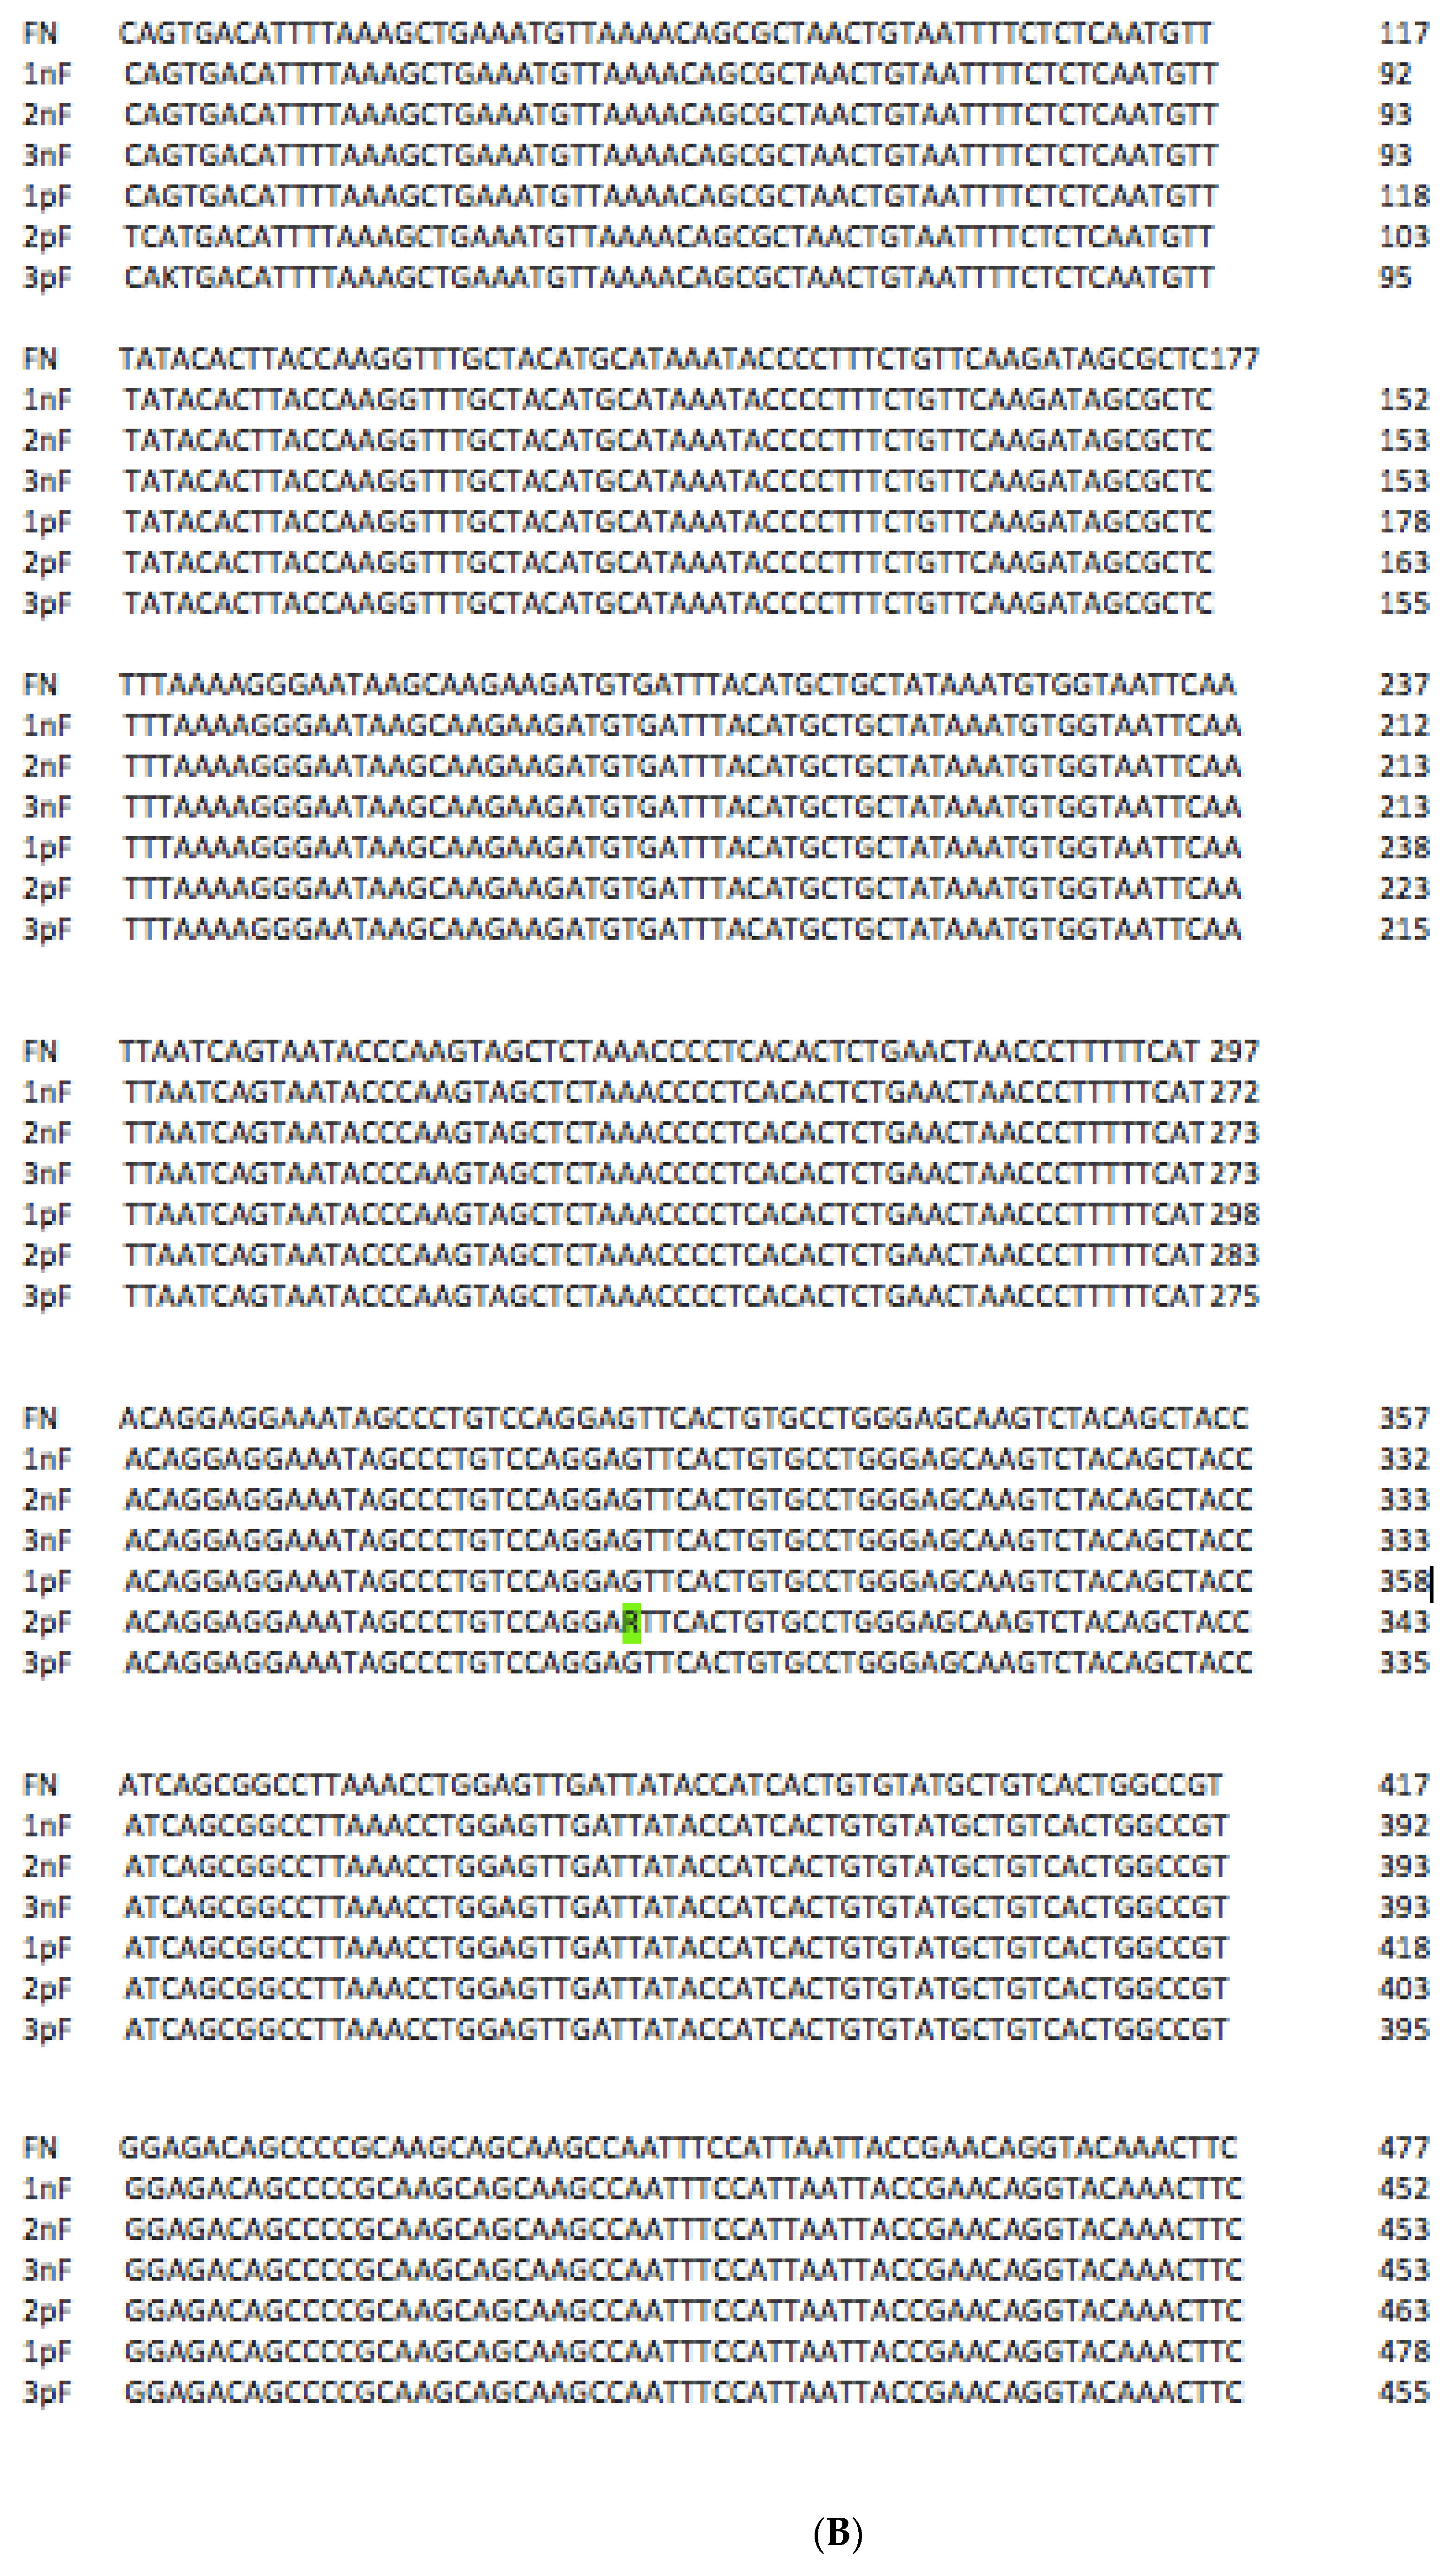

3. Results and Discussion